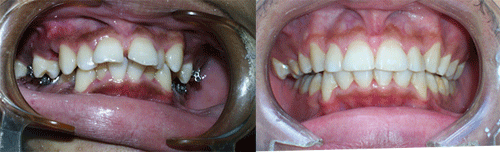

Protruded teeth (bucked teeth) happen when either the upper jaw is too far forward, the lower jaw is too far back, or a combination of both. Expert analysis allows us to determine the cause of the protrusion, and the most effective treatment plan.

With this type of bite, the front teeth are very protuded, and makes these delicate teeth highly prone to trauma, injury, and even premature tooth loss.

We have a number of different options and appliance types for correcting protruded teeth. The photos below illustrate protruded teeth, and the corrections in our patients.